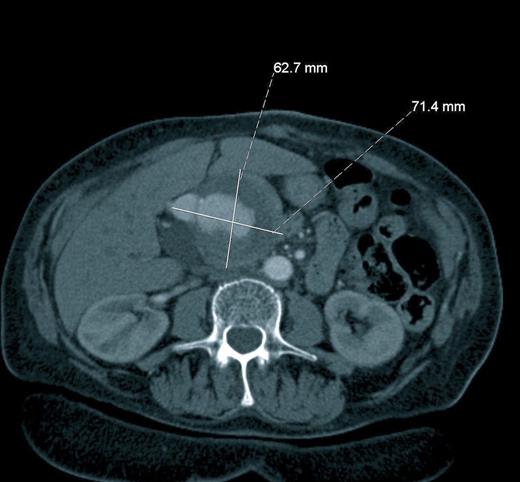

A 74 year-old female with a background of diverticular disease, hypertension, and type 2 diabetes mellitus was admitted with a three-day history of rectal bleeding. On admission the patient was haemodynamically stable with a pulsatile, non-tender mass palpable in the epigastrium and tenderness in the left iliac fossa. No bruit was heard on auscultation. She underwent a CT scan, which revealed an incidental finding of a large saccular aneurysm involving the common hepatic artery and the hepatic artery proper, measuring 6.2 x 7.1 x 7.5cm in maximum dimensions (Figure 1). In addition, multiple focal dilatations of medium-sized visceral arteries (including the splenic artery and left renal artery) were identified.

Axial Computerised Tomography scan after administration of intravenous contrast showing a giant hepatic artery aneurysm